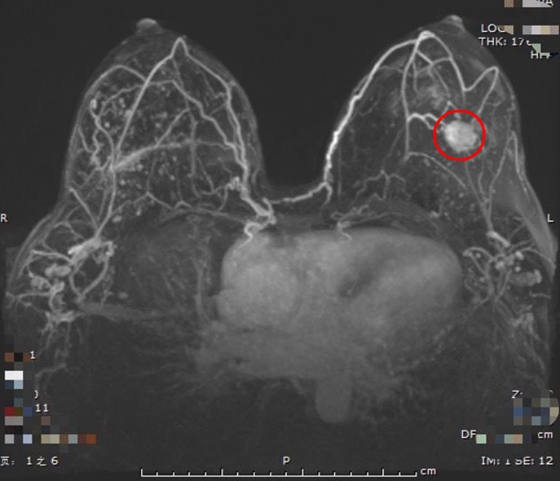

随着乳腺癌在中国呈现逐渐年轻化的发病趋势,乳腺癌已成为女性的头号杀手。在乳腺癌治疗领域,国内绝大部分的女性出于对肿瘤的恐惧而选择切除乳房,随着发病人数增长,失乳女性群体正在逐渐壮大。 近...